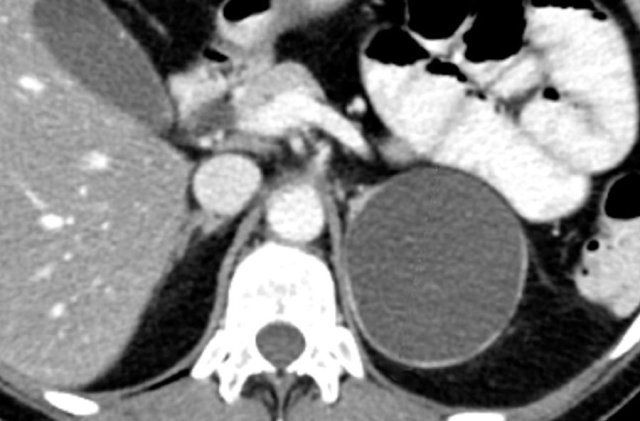

Axial and coronal CT images in a patients with a right adrenal carcinoma and extensive IVC invasion.

The coronal image also shows tumor extension into the right renal vein.

Axial and coronal CT images of another patient with an adrenal carcinoma with extensive IVC invasion (yellow arrow).

IVC and renal vein tumor invasion are seen in up to 20% of patients.